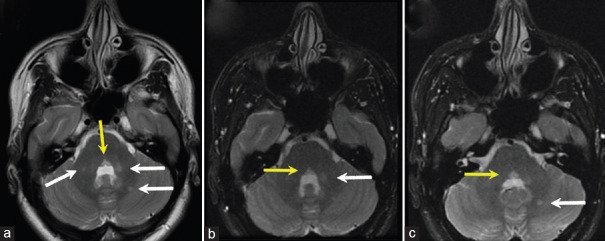

多发性硬化症(MS)是影响中枢神经系统的最常见的脱髓鞘疾病。它的表现多种多样,通常会影响视觉系统。许多多发性硬化症患者会出现视力下降、复视、眼球震颤和眼球运动异常。然而,双侧水平凝视麻痹却极为罕见。我们为大家介绍一例 24 岁女性患者的病例,她来到我们的儿童眼科门诊就诊,主诉双侧水平凝视麻痹、畏光和眼痛 2 天。虽然患者有多发性硬化症家族史,但没有类似或既往的主诉,既往病史和手术史也不突出。检查发现,她的双侧水平囊回和追视功能完全丧失,垂直囊回和追视功能稍有受限。她没有眼球震颤或偏斜,其他颅神经(CN)完好无损。她的眼部生命体征正常,矫正视力为 20/20,全色觉。其他身体和神经系统检查均无异常。转到神经内科后,磁共振成像显示深部白质、脑桥和中脑有多处高强度病变。成像结果与临床表现的相关性证实了临床孤立综合征的诊断。经过脉冲类固醇治疗和五次血浆置换后,患者的眼外肌运动(EOM)明显好转,但同时出现了35棱镜屈光度的后天性内斜视。她接受了右内侧直肌肉毒毒素注射,病情得到明显改善,并在注射后的最后两个月随访中实现了视力矫正。

Multiple sclerosis (MS) is the most common demyelinating disease affecting the central nervous system. It has a wide range of manifestations and commonly affects the visual system. Many patients with MS report decreased vision, diplopia, nystagmus, and abnormal ocular motility. Nevertheless, bilateral horizontal gaze palsies are exceptionally rarely seen. We present the case of a 24-year-old female who came to our pediatric ophthalmology clinic complaining of bilateral horizontal gaze palsy, photophobia, and eye pain for 2 days. Although the patient had a family history of MS, there was no similar or previous complaint, with an unremarkable past medical and surgical history. During the examination, she was found to have a complete bilateral absence of horizontal saccade and pursuit, with slight limitations in vertical ones. There was no nystagmus or skew deviation, and the rest of the cranial nerves (CNs) were intact. Her ocular vital signs were normal, and her corrected visual acuity was 20/20 with full-color vision. The rest of the physical and neurological examinations were unremarkable. After referral to neurology, the magnetic resonance imaging showed multiple hyperintense lesions in deep white matter, pons, and midbrain. The correlation of imaging findings with clinical presentation confirmed the diagnosis of a clinically isolated syndrome. Extra-ocular motility (EOM) significantly improved after pulse steroid therapy and five sessions of plasma exchange, but the patient developed 35 prism diopter of acquired concomitant esotropia. She underwent a right medial rectus botulinum toxin injection which dramatically improved her condition, and became orthotropic during the last 2 months of follow-up after the injection.